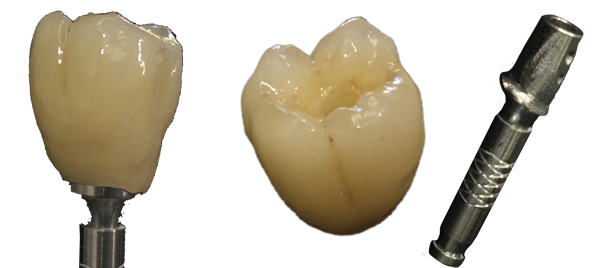

Nous vous proposons des réalisations scéllées, transvissées, transvissées-collées, unitaire ou en bridge, que ce soit tout céramique :

ou en céramo-métallique :